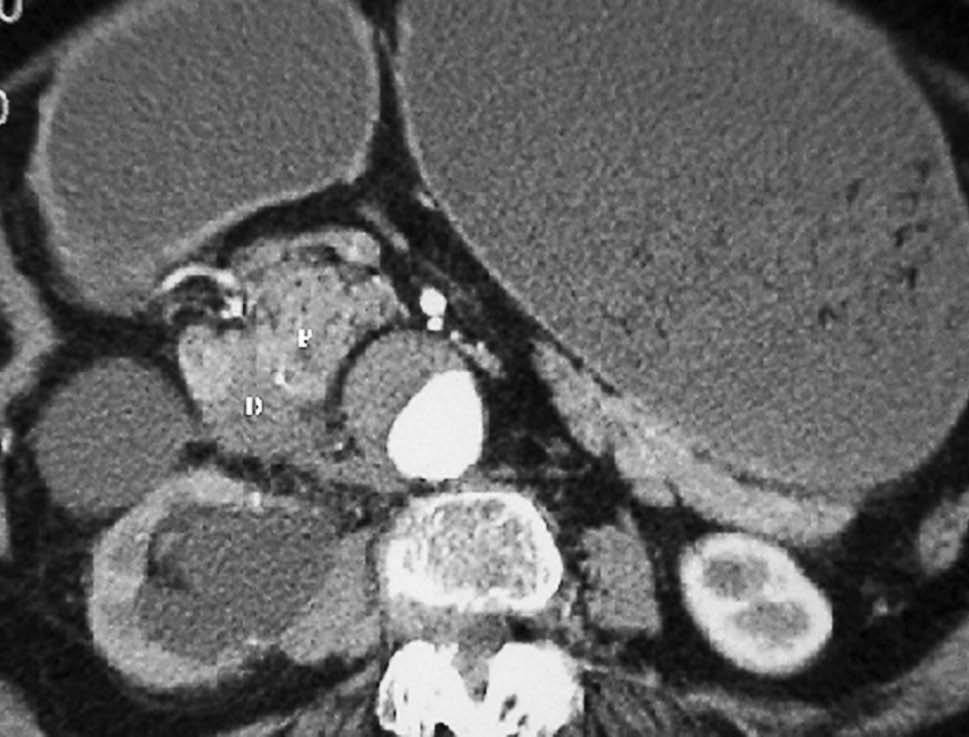

Fig. 9--Diverticulitis duodenal. (A) En la ecografía se observa un divertículo (flechas) con engrosamiento de pared duodenal (D) y alteración de la grasa adyacente (*). (B) Tomografía computarizada de otro paciente con inflamación de divertículo duodenal. Se oberva una lesión quística (punta de flecha) de pared gruesa y borrosa, con material en su interior. P: Páncreas.

Fig. 12--Pancreatitis del surco. Tomografía computarizada con contraste intravenoso. Lesión hipodensa (*), mal definida, que oblitera el plano graso normal entre páncreas (P) y duodeno (D) y con escaso realce.